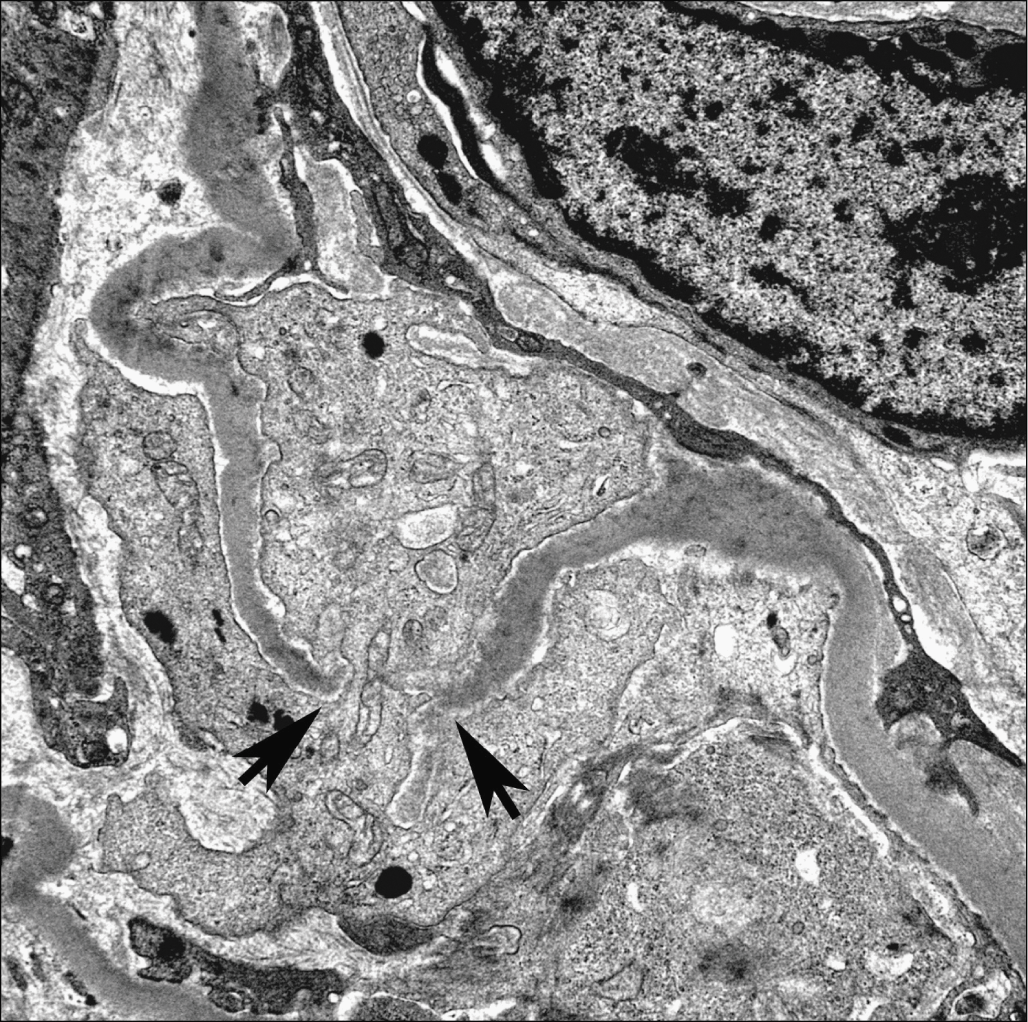

1school of biomedical engineering southern medical university guangzhou 510515 china. The fine structure of the glomerular basement membrane gbm of the rat kidney was studied by means of high resolution scanning electron microscopy. Electron microscopic studies of the kidneys of nzb nzw f 1 bw mice show the presence of electron opaque deposits on the endothelial side of the glomerular basement membrane early in the spontaneous renal disease to which these mice are subject. The fractured surface of glomerular tufts exhibited the inner and outer surface of the gbm uncovered by endothelial and.

Despite numerous excellent and detailed ultrastructural investigations of gbm discontinuities a complete appreciation of their actual number appearance and distribution within a. Cao l1 lu y2 li c1 yang w1. These changes may be missed if glomerular lesions histologically diagnosed as fsgs on light microscopy are not. The gbm can in some ways be viewed as a typical basement membrane.

In order to clarify ultrastructural details electron microscopic observations using negative staining were performed on unfixed human and bovine glomerular basement membranes isolated by a modified method of spiro. Thin glomerular basement membrane nephropathy. Standard electron microscopy techniques have enabled the identification and classification of glomerular diseases based on two dimensional information however complex three dimensional ultrastructural relationships between. Morphological change in glomerular podocytes and the underlying basement membrane are frequently observed in disease irrespective of the underlying molecular etiology.